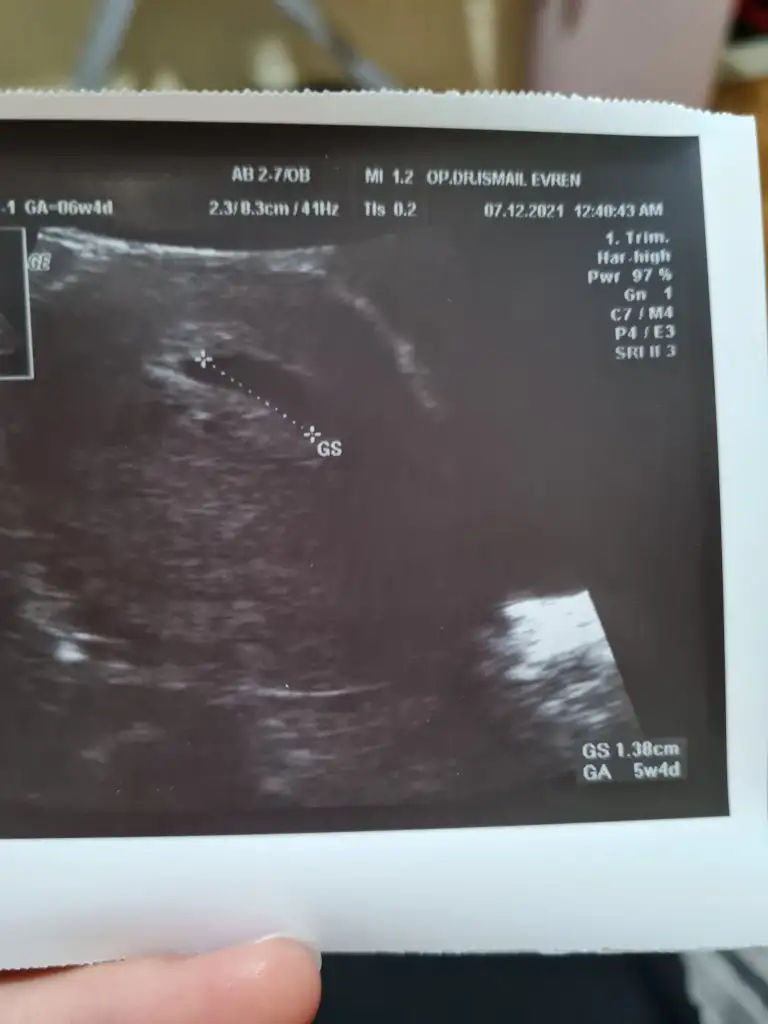

Kizlar merhaba, bugun doktordaydim kese görünüyor keseye göre 5+4 teyim. Son adet tarihime göre 6+2 falandi. Keseyi cuma günü görmüştük ilk başka bir hastanede orda 8.9 mm civarıydi simdi 13 mm olmuş. Eki Görüntüle 2965293 Doktor 15 gün sonrasi için randevu verdi. Fakat yolk kesesiyle ilgili herhangi bir sey soylemedi ben de sormayi unuttum. Sanirim görunse soylerdi. Gören var mı aranızda yada ne zamana kadar görünmemesi normal?

Canım bizim aynıymış bebişler mens tarihine göre senin gibi keseye göre 5+3 dedi bana da ek olarak iyi yere yerleşmiş dedi 9 güm sonra kalp atışı icin çağırdı. insallah sağlıkla kucağımıza alırız bi de benim kesenin gorüntüsü minicik usg çekimi ile alakalı olabilir senin ki daha uzun duruyor masallah hepsine 🧿🤲🥰

Beni 15 gün sonraya çağırdı, çok uzun süre İnşallah her şey yolundadır. İkimizde duyarız kalp atışlarını saglikla alalım kucağımıza İnşallah 🤲 bu arada şimdi fark ettim 12.7 mm falandir yazmaya çalışmıştım yalandır yazmışım, t9 dan oldu herhalde, anlamışsındır sen sanırım 😂